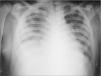

Observaciones clínicasCaso 1Niño de 14 años proveniente de zona rural con evolución de dolor en rodilla derecha de 8 días de intensidad progresiva y falta de apoyo de la extremidad asociado a aparición de signos inflamatorios locales, fiebre alta y síndrome de dificultad respiratoria grave. Inicialmente fue tratado en hospital rural con oxacilina, amikacina y heparina de bajo peso molecular. Llegó a nuestro hospital con la complicación de tromboembolismo pulmonar. Hay antecedente: 12 días previos de contacto con depósito de agua estancada. La hermana presentó un cuadro clínico similar. Al ingreso presentó mal estado general, estado tóxico, edema en miembro inferior derecho y signos de derrame articular en rodilla derecha, fiebre de 39°C, taquicardia, taquipnea y deshidratación. Los exámenes de laboratorio mostraron leucocitosis de 25.000 céls./μl, neutrofilia del 76 %, velocidad de sedimentación globular (VSG) 62mm/h y proteína C reactiva (PCR) 194mg/dl. El Doppler de la extremidad inferior evidenció trombosis de la vena femoral superficial en toda su extensión y de la ilíaca (fig. 1). La radiografía de tórax reveló signos sugestivos de tromboembolismo pulmonar (fig. 2), que se confirmó mediante un angiotomografía computarizada (angio-TC) (fig. 3). Se inició anticoagulación, con heparina en dosis de carga de 75 U/kg i.v. en 10min, y mantenimiento a 20 U/kg/h y tratamiento antibiótico con oxacilina y amikacina. Se practicó artrotomía de la rodilla y se encontró material purulento. El cultivo fue positivo a Staphylococcus aureus sensible a oxacilina, rifampicina, clindamicina y resistente a ampicilina, hallándose el mismo germen en los hemocultivos. Se realizó estudio inmunológico y de coagulación, encontrándose dentro de límites normales la proteína C, S, y fibrinógeno. La AT III se encontró disminuida, con valores de 17,8 (normal 27,7-38,3). Proteínas totales, albúmina y procalcitonina, inmunoglobulinas A, G, M, E y CD4 eran normales, como las pruebas de función renal. Gota gruesa fue negativa. Requirió tratamiento en la unidad de cuidados intensivos (UCI) con soporte inotrópico, ventilación mecánica y antibiótico. Se inició estreptocinasa, la cual fue suspendida a causa de sangrado pulmonar masivo. Se colocó filtro en la vena cava por persistencia de fenómenos de tromboembolismo de repetición. Se agregó rifampicina y se cambió de oxacilina a vancomicina por pobre respuesta y persistencia de estado séptico. El eco-Doppler de control mostró persistencia del trombo con mínima regresión. Mejoró sus síntomas respiratorios a los 12 días del ingreso. Por persistencia de dolor en la zona del fémur distal derecho se realizó gammagrafía ósea, que evidenció hipercaptación metafisaria distal femoral compatible con osteomielitis. Un nuevo eco-Doppler control mostró ligera mejoría del trombo 16 días posterior al primer examen. Se completó tratamiento antibiótico intravenoso durante 40 días y anticoagulación plena con heparinas de bajo peso molecular. Posteriormente, recibió dosis profilácticas durante 6 meses con evolución satisfactoria.